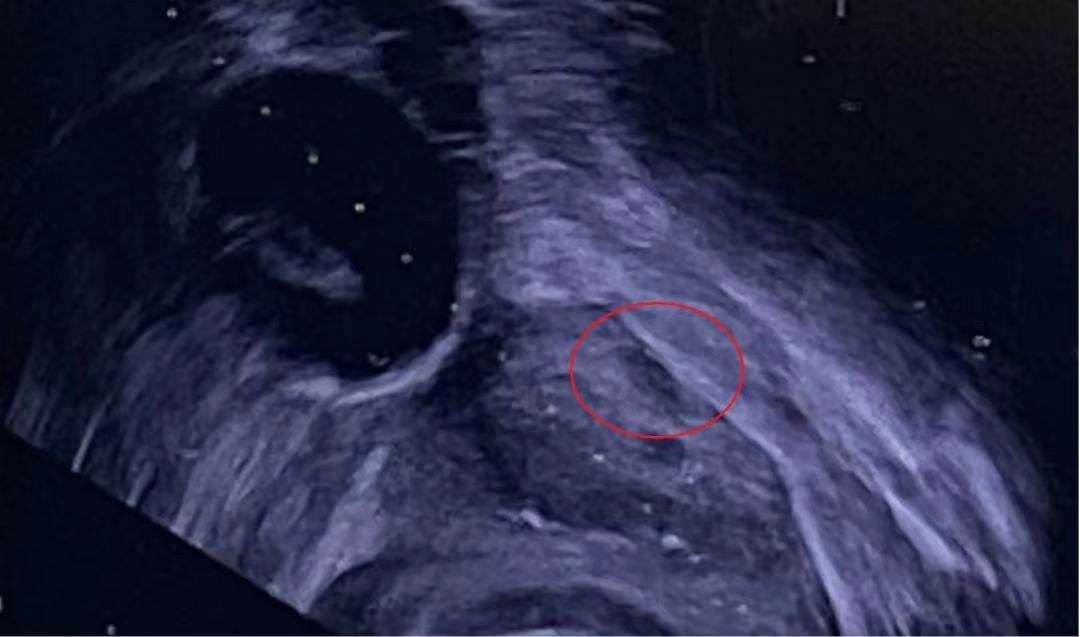

经研究,科室决定为该患者行经会阴前列腺靶向穿刺术。以0.5cm可疑病灶为靶病灶,进行超声下精准定位(图1),经会阴进针,以适当角度绕过耻骨后,再向前列腺腹侧调整方向继续进针,在超声引导下抵达病灶附近。贴紧靶病灶穿刺活检(图2),成功取得肿瘤组织样本,并于术后病理检测中确认为早期前列腺癌。该患者发现早、病灶小、未发生临近器官侵犯和远处转移,具备根治手术的条件,计划行腹腔镜下前列腺癌根治术,以彻底切除恶性肿瘤,使患者重获健康。

图2:靶向穿刺